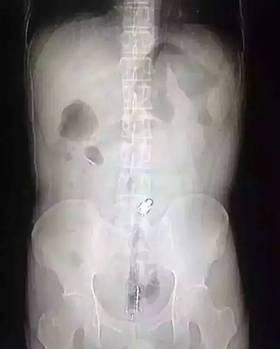

“因為物體邊緣比較光滑,手術的時候,我們兩個人合作,一個人順著肚子一點點推,推到肛門口,我把異物拿了出來,大概花了十分鐘時間。”郁峰說,這名男子運氣算好的,因為根據(jù)拍片檢查,當時那根振動棒已經(jīng)擠到了肚臍的部位,情況其實已經(jīng)相當危險。醫(yī)生提醒 “那根振動棒有20公分,人的直腸只有18公分,它的長度已經(jīng)超過直腸了,到達乙狀結(jié)腸,會引起腸子破裂壞死,如果破了就會有生命危險 。 ”